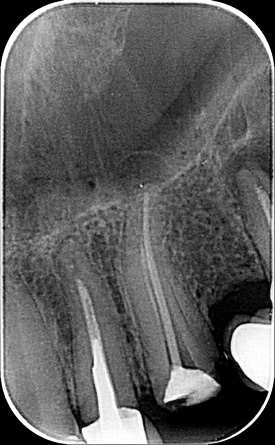

СЛИКЕ